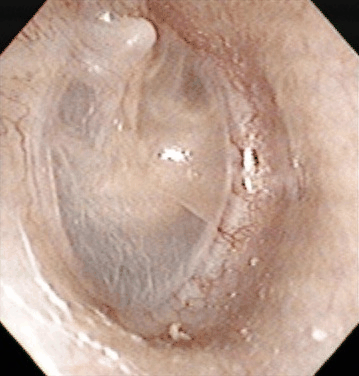

Otitis Media with Effusion